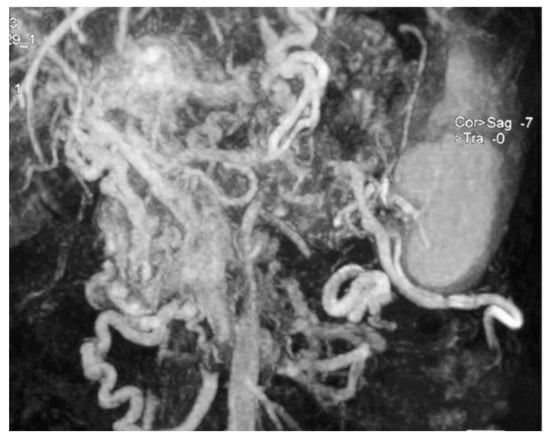

Among 239 patients with a histologically confirmed pNET observed in our unit during the study period, seven (2.9%) patients had a 5-HT-secreting pNET. The study population consisted of four men and three women, with a median age of 64 (range 38–69) years. Only two patients had symptoms related to a carcinoid syndrome with flushing and diarrhoea (Figure 1); all the others presented with a non-functioning pNET. The leading presenting symptom was weight loss in three (43%) patients, and two (29%) patients complained about abdominal pain (Figure 2). One patient had a cervical lymphadenopathy, and another presented with jaundice and ascites due to portal vein thrombosis (Figure 3).

Figure 3. Abdominal magnetic resonance imaging showing several huge mesenteric and left gastric vein compensation collateral circles due to portal vein thrombosis and portal hypertension (case n.6).